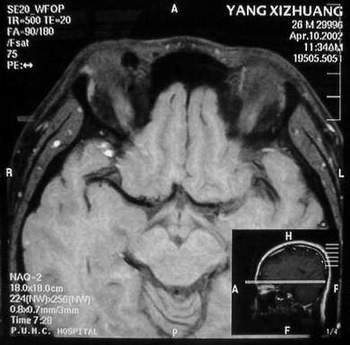

MRI及增强结果如下:

患者压颈及其它Valsava试验结果阴性。从MRI分析,在T1、T2、T+C检查该支血管均为明显流空现象,说明该血管血流速度很快,而从走行和分布看,眼上静脉可能性很大。也许也不能除外异常的眼动脉或异常血管。眶内主要可能的血管病变包括颈内动脉海绵窦瘘(高流窦)、AVM、眼眶静脉曲张、海绵状血管瘤、静脉性血管瘤、毛细血管瘤和眶内动脉瘤。。 1、颈内动脉海绵窦瘘:该患者临床有一部分支持该诊断。但从影像分析,海绵窦未见明显扩张;眼外肌未见明显充血扩张的长T1、长T2信号;颈内动脉海绵窦瘘常可见继发到血栓,可见到短T1、长T2的血栓信号。 2、眼眶静脉曲张:该疾患一般常见于小儿。该患大多数会出现Valsava试验阳性,间歇性突眼。不符合该患。影像学检查,于曲张静脉内常可见血栓和静脉石。所以不符合该患。 3、AVM:患者目前的影像学资料尚不全面,但可符合该诊断。临床上改病常见于30岁左右年轻人,单侧发病,于本患较符合。问题在于临床没有明确的血管杂音,似乎难以解释。 4、该患影像学与海绵状血管瘤差别很大,所以可基本排除此诊断。 5、静脉性血管瘤和毛细血管瘤:MRI中等T1、长T2信号,较易与本病鉴别。 6、眶内动脉瘤:我觉得患者并不能排除本病,但同样,由于波动性阴性,似乎也难以解释。 纵上所述:本人觉得,患者AVM可能性较大,同时不能除外眶内动脉瘤。 关于进一步检查,我觉得DSA价格过于昂贵。是否可先进行彩色多普勒检查,首先可以明确是静脉系统还是动静脉瘘抑或是动脉瘤。第二步,可进行MRA检查,可以清楚地显示海绵窦地相关关系,并可借此诊断或排除颈内动脉海绵窦瘘。如还需第三部检查,可进行MRV检查,对静脉系统进一步评价。三种检查总共的费用2000多圆,但给予我们的信息量已经很丰富了。 敬请各位医师提出自己的见解。 谢谢!